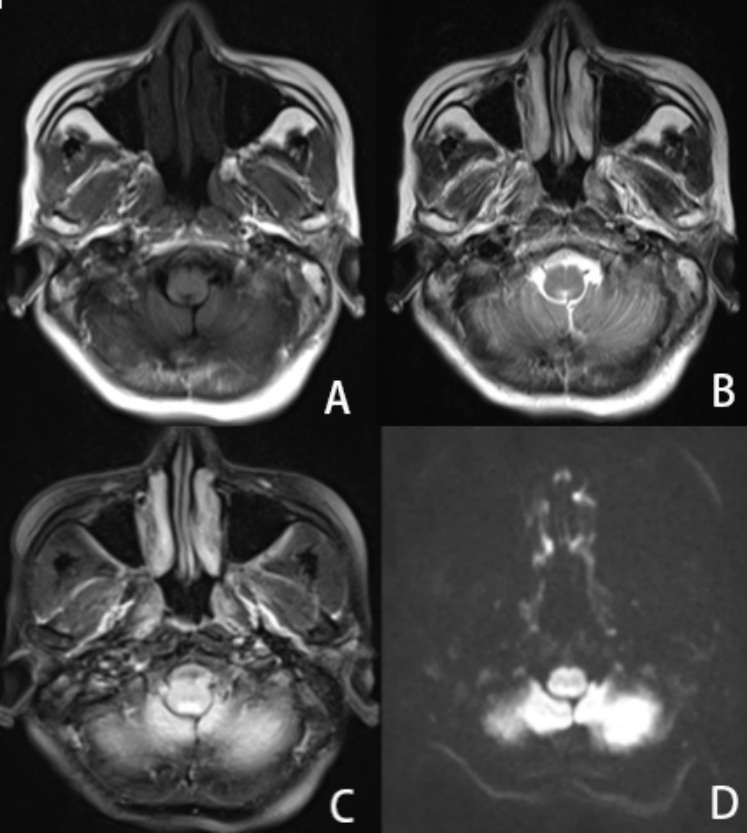

患者9月7日入住我院EICU,予以补液、护胃等对症治疗后症状未见明显好转,行腰椎穿刺术示:潘氏试验阳性,白细胞数19 × 106/L,蛋白定量0.85 g/L,提示蛋白细胞分离(见表1),考虑吉兰巴雷可能性大转入我院神经内科治疗。9月8日转入我院神经内科后予以泮托拉唑护胃、间苯三酚解痉,呃逆、呕吐症状较前稍改善,9月10日~9月14日予以丙种球蛋白20 mg ivbydrip Qd调节免疫治疗后呕吐、呃逆及双下肢乏力症状稍缓解。9月13日复查腰椎穿刺术示:细胞数正常,蛋白定量0.89 g/L,潘氏试验阳性(见表2)。完善头颅MRI + DWI示:腹侧丘脑、双侧视交叉、延髓背侧、右侧视神经周围多发异常信号,考虑脱髓鞘病变可能性大(见图1),颈胸腰椎增强MRI示:1. 颈胸椎脊髓内多发异常信号灶;2. 腰5、骶1层面椎管内占位,性质待定(见图2)。

A:T1W1像;B:T2W1像;C:T2 Flair像;D:DWI像

Figure 1. Brain MRI with DWI shows multiple abnormal signals in the ventral thalamus, bilateral optic chiasm, dorsal medulla oblongata, and surrounding the right optic nerve

1. 头颅MRI + DWI示:腹侧丘脑、双侧视交叉、延髓背侧、右侧视神经周围多发异常信号